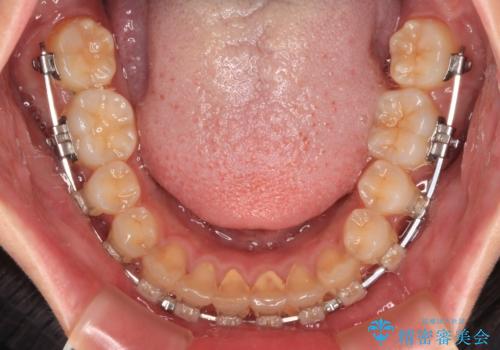

捻れて前に出ている前歯 ワイヤー装置での非抜歯矯正

- 捻れて前に出ている上顎前歯と全体的なデコボコを気にして来院された患者様です。

口元の突出感は強くなかったため非抜歯矯正での対応となりますが、捻転を改善する際に上顎前歯が前突する可能性があったため、上顎臼歯部にアンカースクリューを使用して、歯列が前方に転位しないようにすることとしました。

ワイヤー矯正でもインビザラインでも対応可能でしたが、上顎歯列が前方位であるときには、ワイヤー矯正の方がより良い仕上がりとなる可能性が高いため、ワイヤー矯正をおすすめいたしました。

舌の突出癖がなかなか改善されず、上下前歯が接触するようになるまでに長期間を要しました。